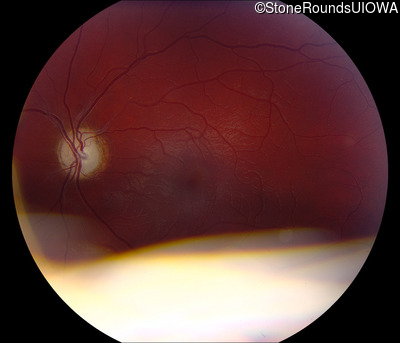

Age at visit: 17 years

This 17 year old male had normal vision until about 6 months earlier when he began to lose central vision. The left eye may have been affected prior to the right eye.